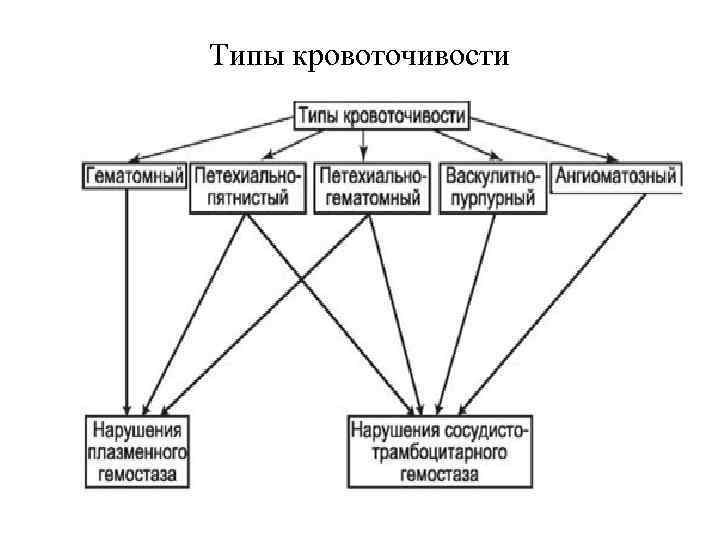

Геморрагические диатезы (2 уровень) В этом разделе мы изучаем три заболевания: 1. Аутоиммунная тромбоцитопеническая пурпура 2. Гемофилия 3. Геморрагический васкулит. В обеспечении нормального гемостаза участвуют тромбоциты (тромбоцитарный компонент), факторы свертывания крови (плазменный компонент) и сосудистая стенка (сосудистый компонент). Фибринолитическая система обеспечивает растворение избыточных тромботических масс

Типы кровоточивости